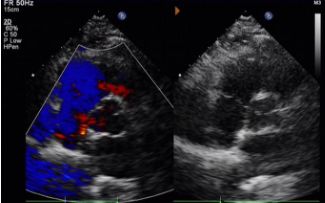

Jour 1 à 9 mois:

Aucun shunt résiduel n'a été observé.

Réduction progressive de l'échogénicité du dispositif.